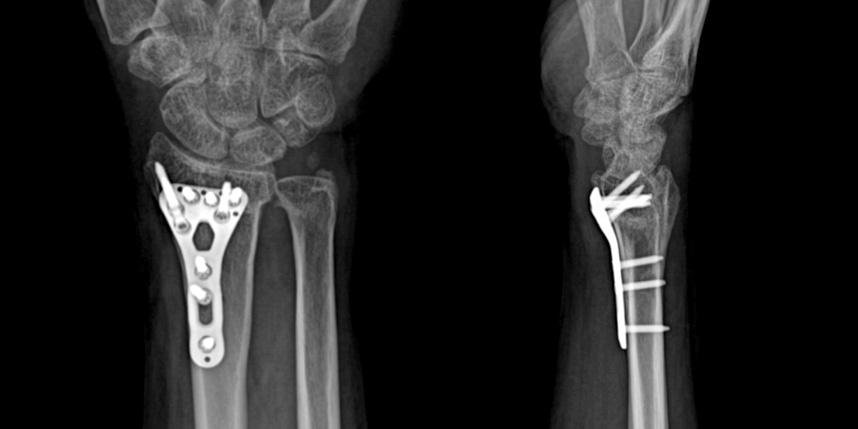

손목 골절

* 환자에게 받은 소중한 자료입니다.